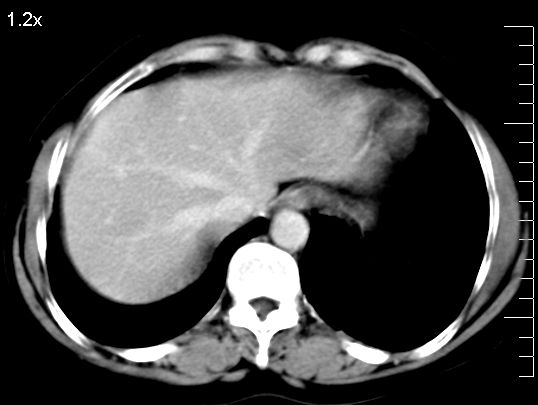

标题: CT10752:F,52岁,反复上腹部疼痛,平扫+增强. [打印本页]

f、52岁,反复上腹部疼痛2年。肺结核病史10多年,胸片双上肺结核纤维化。

ct表现:

肝大小形态未见异常,肝内外胆管无扩张,肝s8段见一动脉期明显血管样强化结节,门脉期呈高密度,延迟期呈等密度,胆囊不大,增强扫描见胆囊及胆囊颈管壁增厚,有强化。

诊断:

1、胆囊炎(轻度)。

2、肝s8段结节,考虑小血管瘤。

4、目前ct表现尚不能解释患者上腹部疼痛,建议上消造影检查,除外胃炎等疾患。

肝右上叶血管瘤!

考虑肝右叶前上段包膜下小血管瘤。

肝上近膈顶小血管瘤